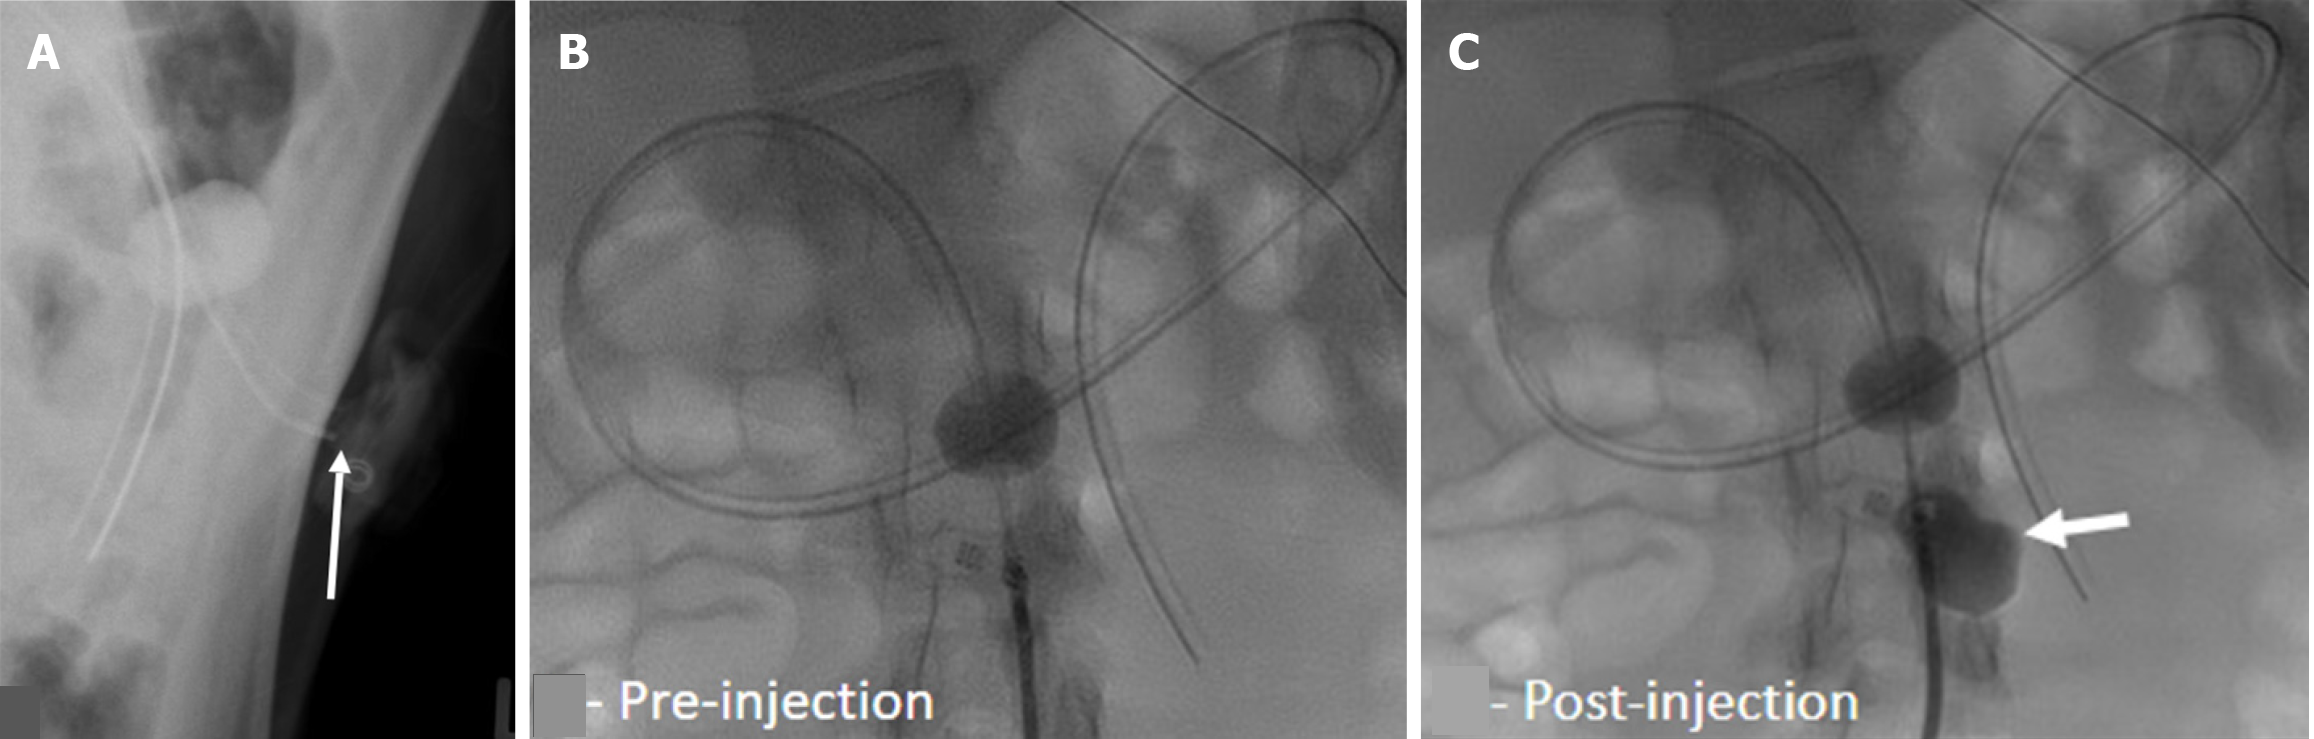

Figure 3 Free peritoneal spillage of contrast.

A: Lateral radiograph of a 1-year-old with recently exchanged tube. Injected contrast pools in the intraperitoneal cavity (arrowhead) which does not follow the stomach contour with outlining of bowel loops (arrow); B: Frontal radiograph irregular or angular margins of the injected contrast (arrow) (multiple black dots outlining the air filled stomach); C: Frontal radiograph of another 4-year-old boy demonstrates similar extrinsic outlining of bowel loops.